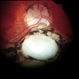

- RD, chorioretinal coloboma

- Color fundus photograph of a 43 year old male post retinal detachment surgery in a case of iridofundal coloboma.